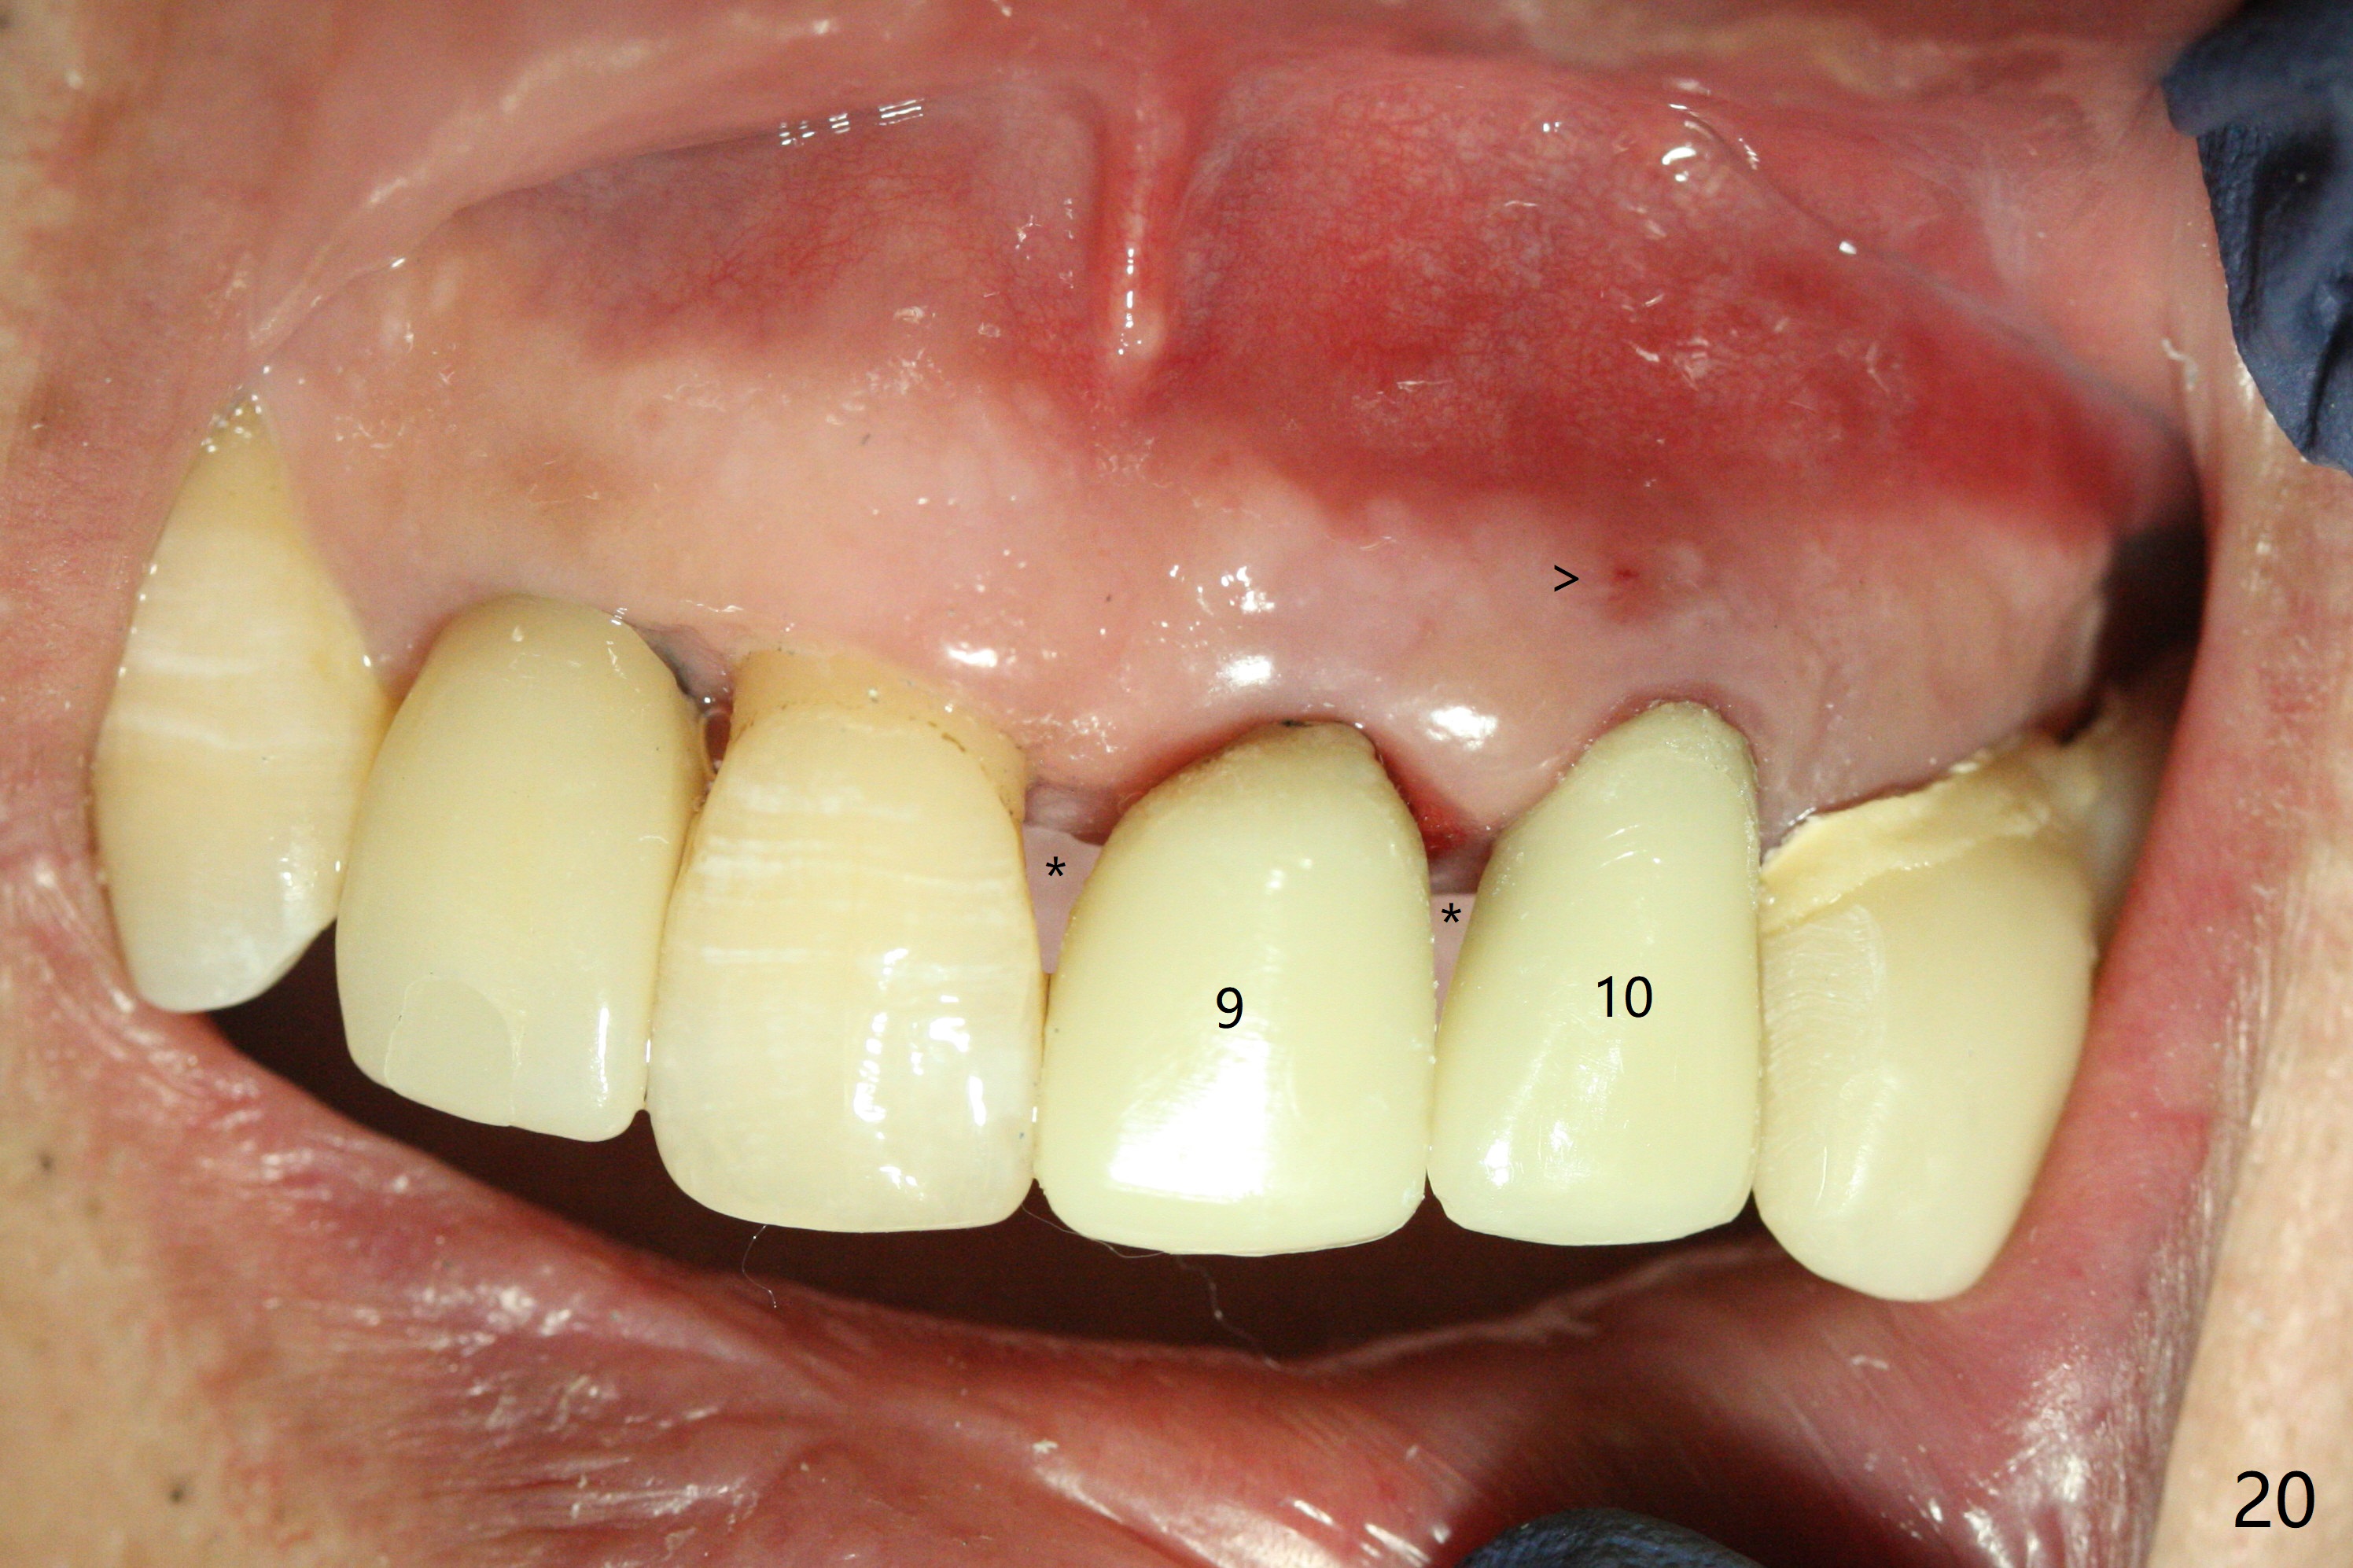

The patient returns 8 days postop, uncomfortable with overhang in the provisional (Fig.10 *). The sockets appear to be healing with loose bone graft (Fig.11) when the provisional is removed for trimming (Fig.12). Six (for #7,13) and seven (#9-11,15) months postop, the soft (Fig.13,17) and hard (Fig.14-16,18) tissues heal. It appears that the trajectory at #9,11 and 13 should be changed by using angled abutments (Fig.18,19 (panoramic X-ray taken 2 months earlier)) before provisional and final restoration.

There is 1-2 thread exposure mesial and distal at #10 two years postop (Fig.20'), which may be related to the small fistula labially (Fig.20 >). It appears that the implant at #10 was placed too high (Fig.21) and labially (Fig.22). In fact the bridge fractures between #12 and 13 during pandemic.